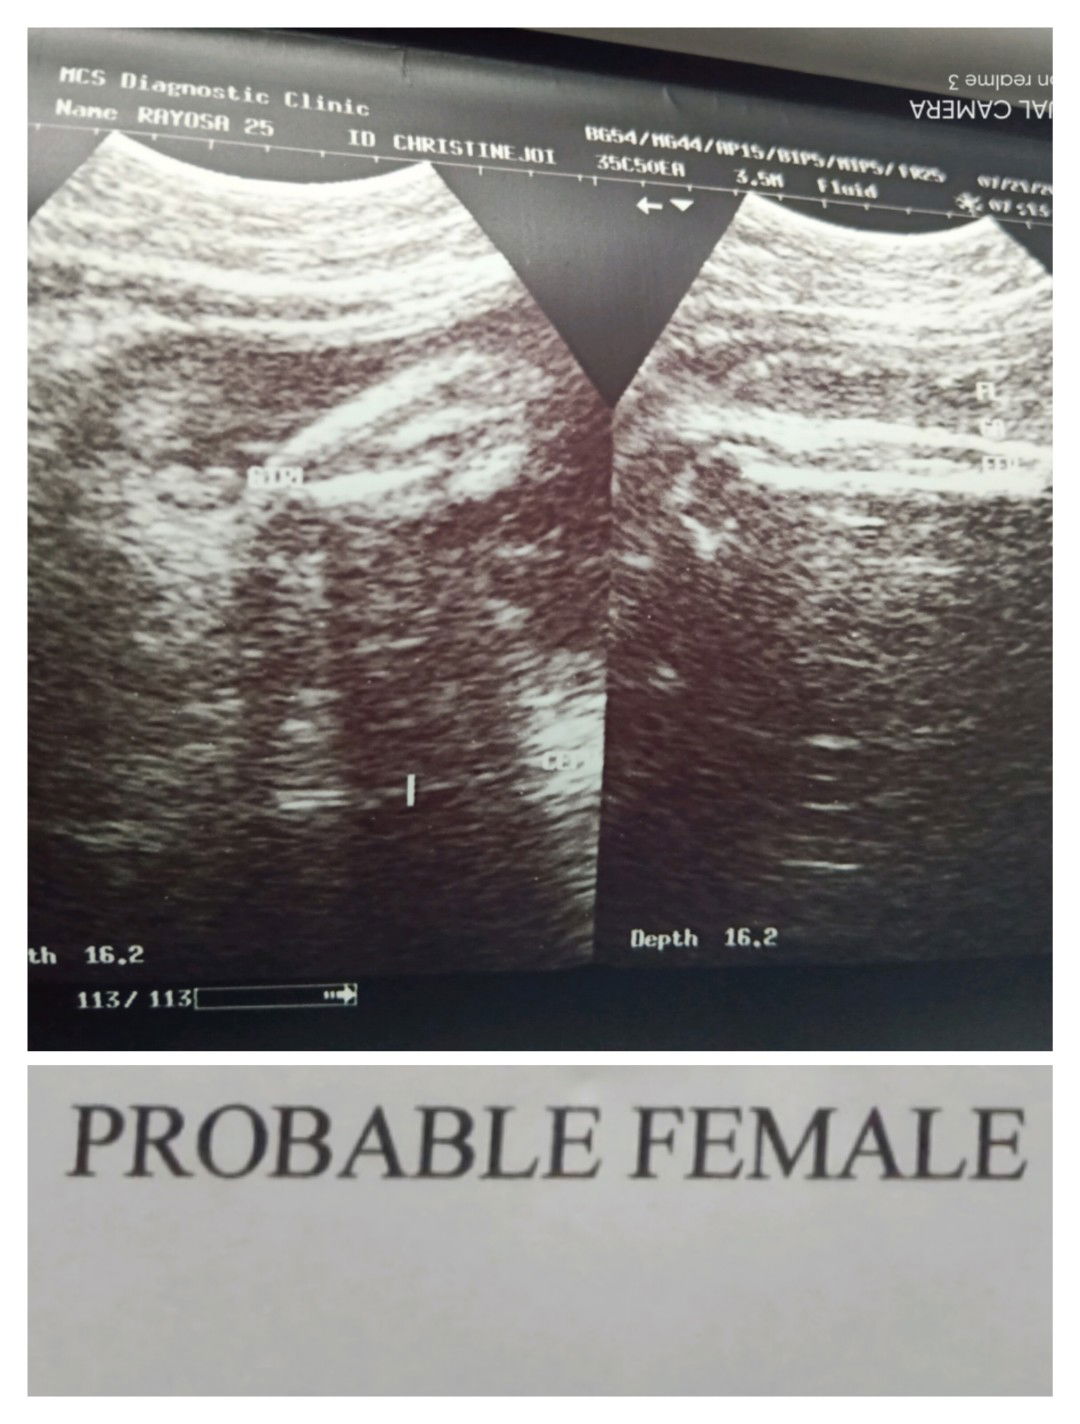

32 weeks & 6 Days

Finally π Girl talaga sya . nag alinlangan kasi ako nung unang ultrasound ko kasi Breech position tapos nakataob si baby pero sabe parang Girl So naiisip ko naman nun baka mamaya sabe Girl tapos pag nanganak e Boy π Pero eto Girl talaga sya. Team Septemberπ